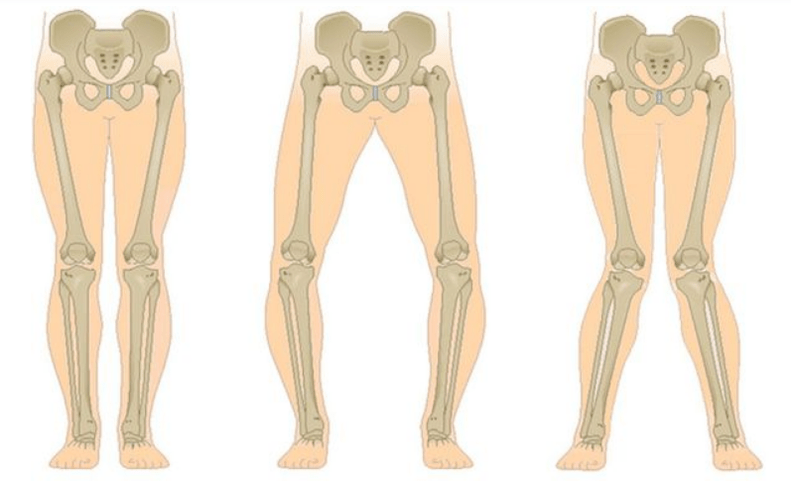

The last stage of gonarthrosis is distinguished by the fact that the pain becomes almost constant, causing anxiety not only when walking, but also at rest, and even at night, when the patient needs to find a comfortable position to sleep.Movement is more limited: it is difficult to fully bend and straighten the leg.Joints become deformed and increase in volume.Valgus (X-shaped) or varus (O-shaped) foot deformities are often observed.The gait becomes unsteady and swaying.In severe cases, crutches or crutches are required.

With arthrosis (osteoarthrosis), in addition to the progressive destruction of cartilage, loss of elasticity and shock-absorbing properties, bone is gradually involved in the process.Under load, sharp edges (exostoses) appear, which are mistakenly considered "salt deposits" - with classic arthrosis, no salt deposits occur.As arthrosis develops, it continues to "eat" the cartilage.Then the bones become deformed, cysts form there, all joint structures are affected, and the legs become bent.

Depending on the number of joints affected, unilateral and bilateral gonarthrosis are distinguished.